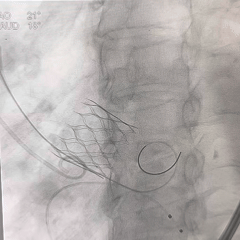

脱钩后造影,瓣膜位置可

外周血管检查,无损伤

TEE短轴,无瓣周漏

TEE长轴,瓣膜深度可